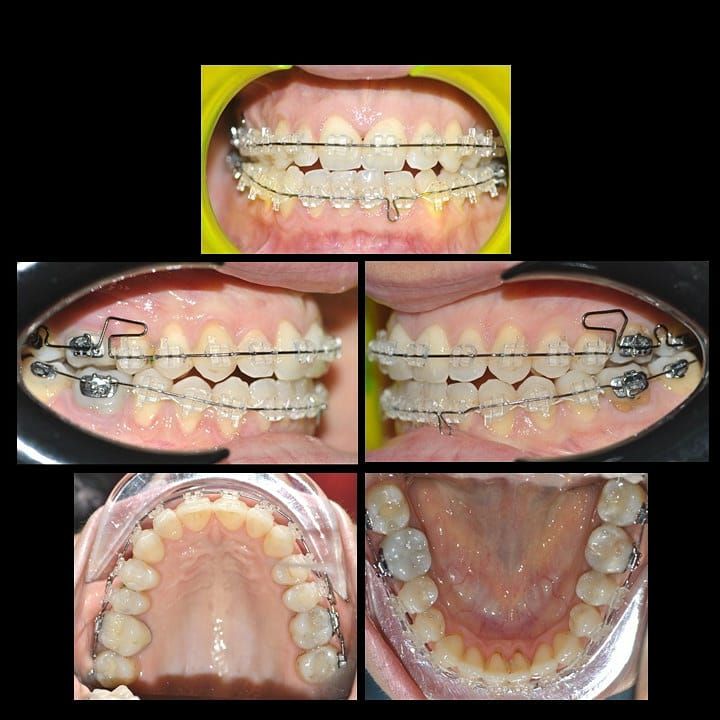

Il dottore ha acquisito una concezione quanto più pratica e moderna della disciplina e utilizza apparecchietti di diversi colori di tipo mobile e fisso, ma anche terapie sia estetiche che invisibili, fiore all’occhiello di poche realtà in Italia. Per terapie estetiche e invisibili si intendono quelle in grado di spostare i denti, senza che traspaia nulla dalla bocca o con stelline e fili bianchi, esattamente come i denti del paziente.

Ma ancora di più l’équipe è in grado di offrire un servizio davvero unico: la tecnica dei retainer attivi. Questa consiste in fili o bottoni che si incollano dietro i denti e che, quindi, nascondono completamente la terapia. Questo tipo di prestazioni aiuta a superare la grande difficoltà psicologica, che spesso si insinua anche negli adulti, di dover spostare i propri denti per un sorriso perfetto: si consideri che tale difficoltà non viene affrontata, il più delle volte, proprio per l’imbarazzo che una apparecchiatura ortodontica genera in chi la usa. Queste tecniche, insieme alle mascherine invisalign invisibili di cui è provider ufficiale e agli attacchi in ceramica, sono tutte quotidianamente utilizzate presso i nostri reparti, in cui è possibile associarle in un discorso multidisciplinare a tutte le altre esigenze della odontoiatria classica.

Foto e video